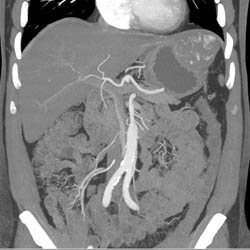

Hepatic Hemangioma Simulates A GIST Tumor of the Stomach- See Full Sequence of Images